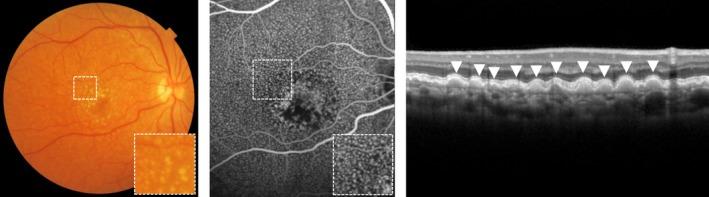

Age-related macular degeneration (AMD) is a degenerative disease of the macula, often leading to progressive vision loss. The rate of disease progression can vary among individuals and has been associated with multiple risk factors. In this review, we provide an overview of the current literature investigating phenotypic, demographic, environmental, genetic, and molecular risk factors, and propose the most consistently identified risk factors for disease progression in AMD based on these studies. Finally, we describe the potential use of these risk factors for personalised healthcare.

While phenotypic risk factors such as drusen and pigment abnormalities become more important to predict disease progression during the course of the disease, demographic, environmental, genetic and molecular risk factors are more valuable at earlier disease stages. Demographic and environmental risk factors such as age and smoking are consistently reported to be related to disease progression, while other factors such as sex, body mass index (BMI) and education are less often associated. Of all known AMD variants, variants that are most consistently reported with disease progression are rs10922109 and rs570618 in CFH, rs116503776 in C2/CFB/SKIV2L, rs3750846 in ARMS2/HTRA1 and rs2230199 in C3. However, it seems likely that other AMD variants also contribute to disease progression but to a lesser extent. Rare variants have probably a large effect on disease progression in highly affected families. Furthermore, current prediction models do not include molecular risk factors, while these factors can be measured accurately in the blood. Possible promising molecular risk factors are High-Density Lipoprotein Cholesterol (HDL-C), Docosahexaenoic acid (DHA), eicosapentaenoic acid (EPA), zeaxanthin and lutein.